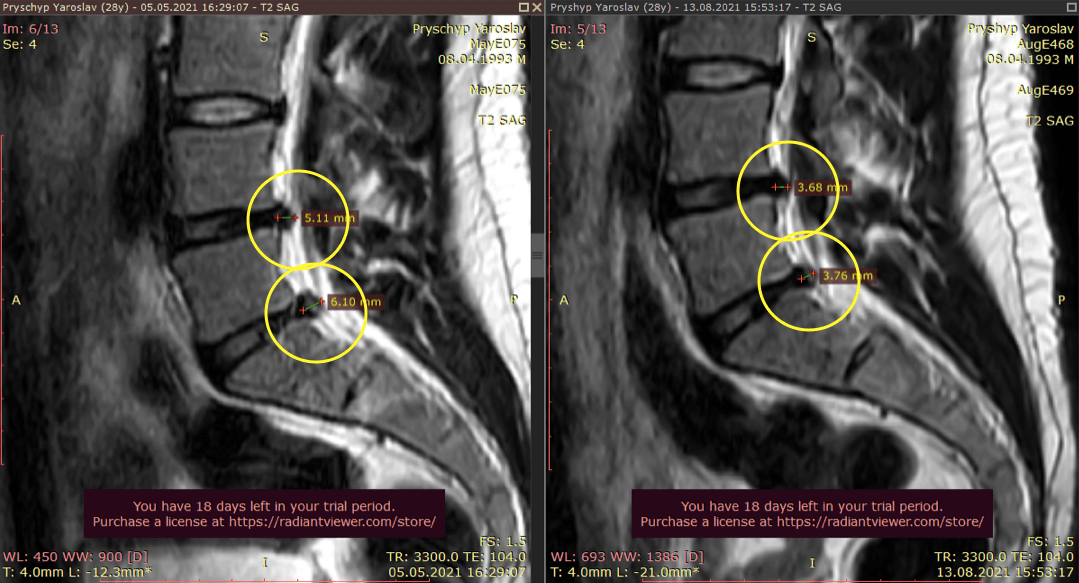

Метод лікування грижі шляхом стимуляції резорбції в Україні був впроваджений у 2020-2021 роках.  Алгоритм оцінки грижі на предмет резорбції, що використовується у клініках – є авторським, розроблений лікарем Боханом А.Ю.